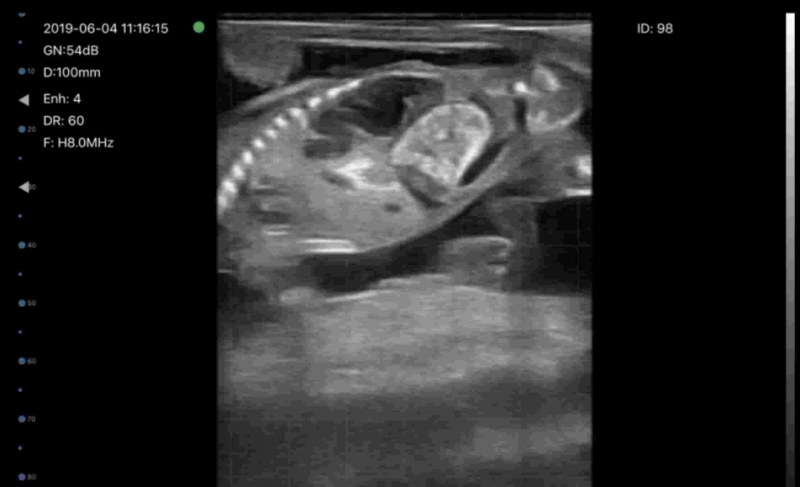

Early pregnancy detection using B-mode as early as day 28

fetal sexing between days 50 and 60.